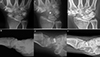

Figure 2 Clinical case of FCR tenodesis over capitate (Ligamentous grip) and Scaphoid excision. A and B. Preoperative wrist X-rays of SNAC stage II (AP and Lateral views). C and D. Postoperative wrist X-rays (AP and Lateral views) after the removal of K-wire (1month). E and F. Postoperative wrist X-rays (AP and Lateral views) after 12.25 years. Source: Dr. Emmanouil Apergis. |

The FCR over-capitate tenodesis was performed using a combined volar and dorsal approach, following the method originally described by Garcia-Elias and later refined by Luchetti et al. [10, 13, 14]. A distally based slip of the flexor carpi radialis tendon was harvested volarly and routed from the volar aspect of the wrist to the dorsal side through the midcarpal interval. After scaphoid excision and radiocarpal realignment, the tendon was passed over the neck of the capitate and looped around the radiotriquetral ligament to create a stabilizing sling. The dorsal limb was secured with non-absorbable sutures, and a dorsal capsular flap was advanced to reinforce the construct. This technique was selected in patients with preserved radiolunate and capitolunate cartilage who preferred a motion-preserving reconstruction.